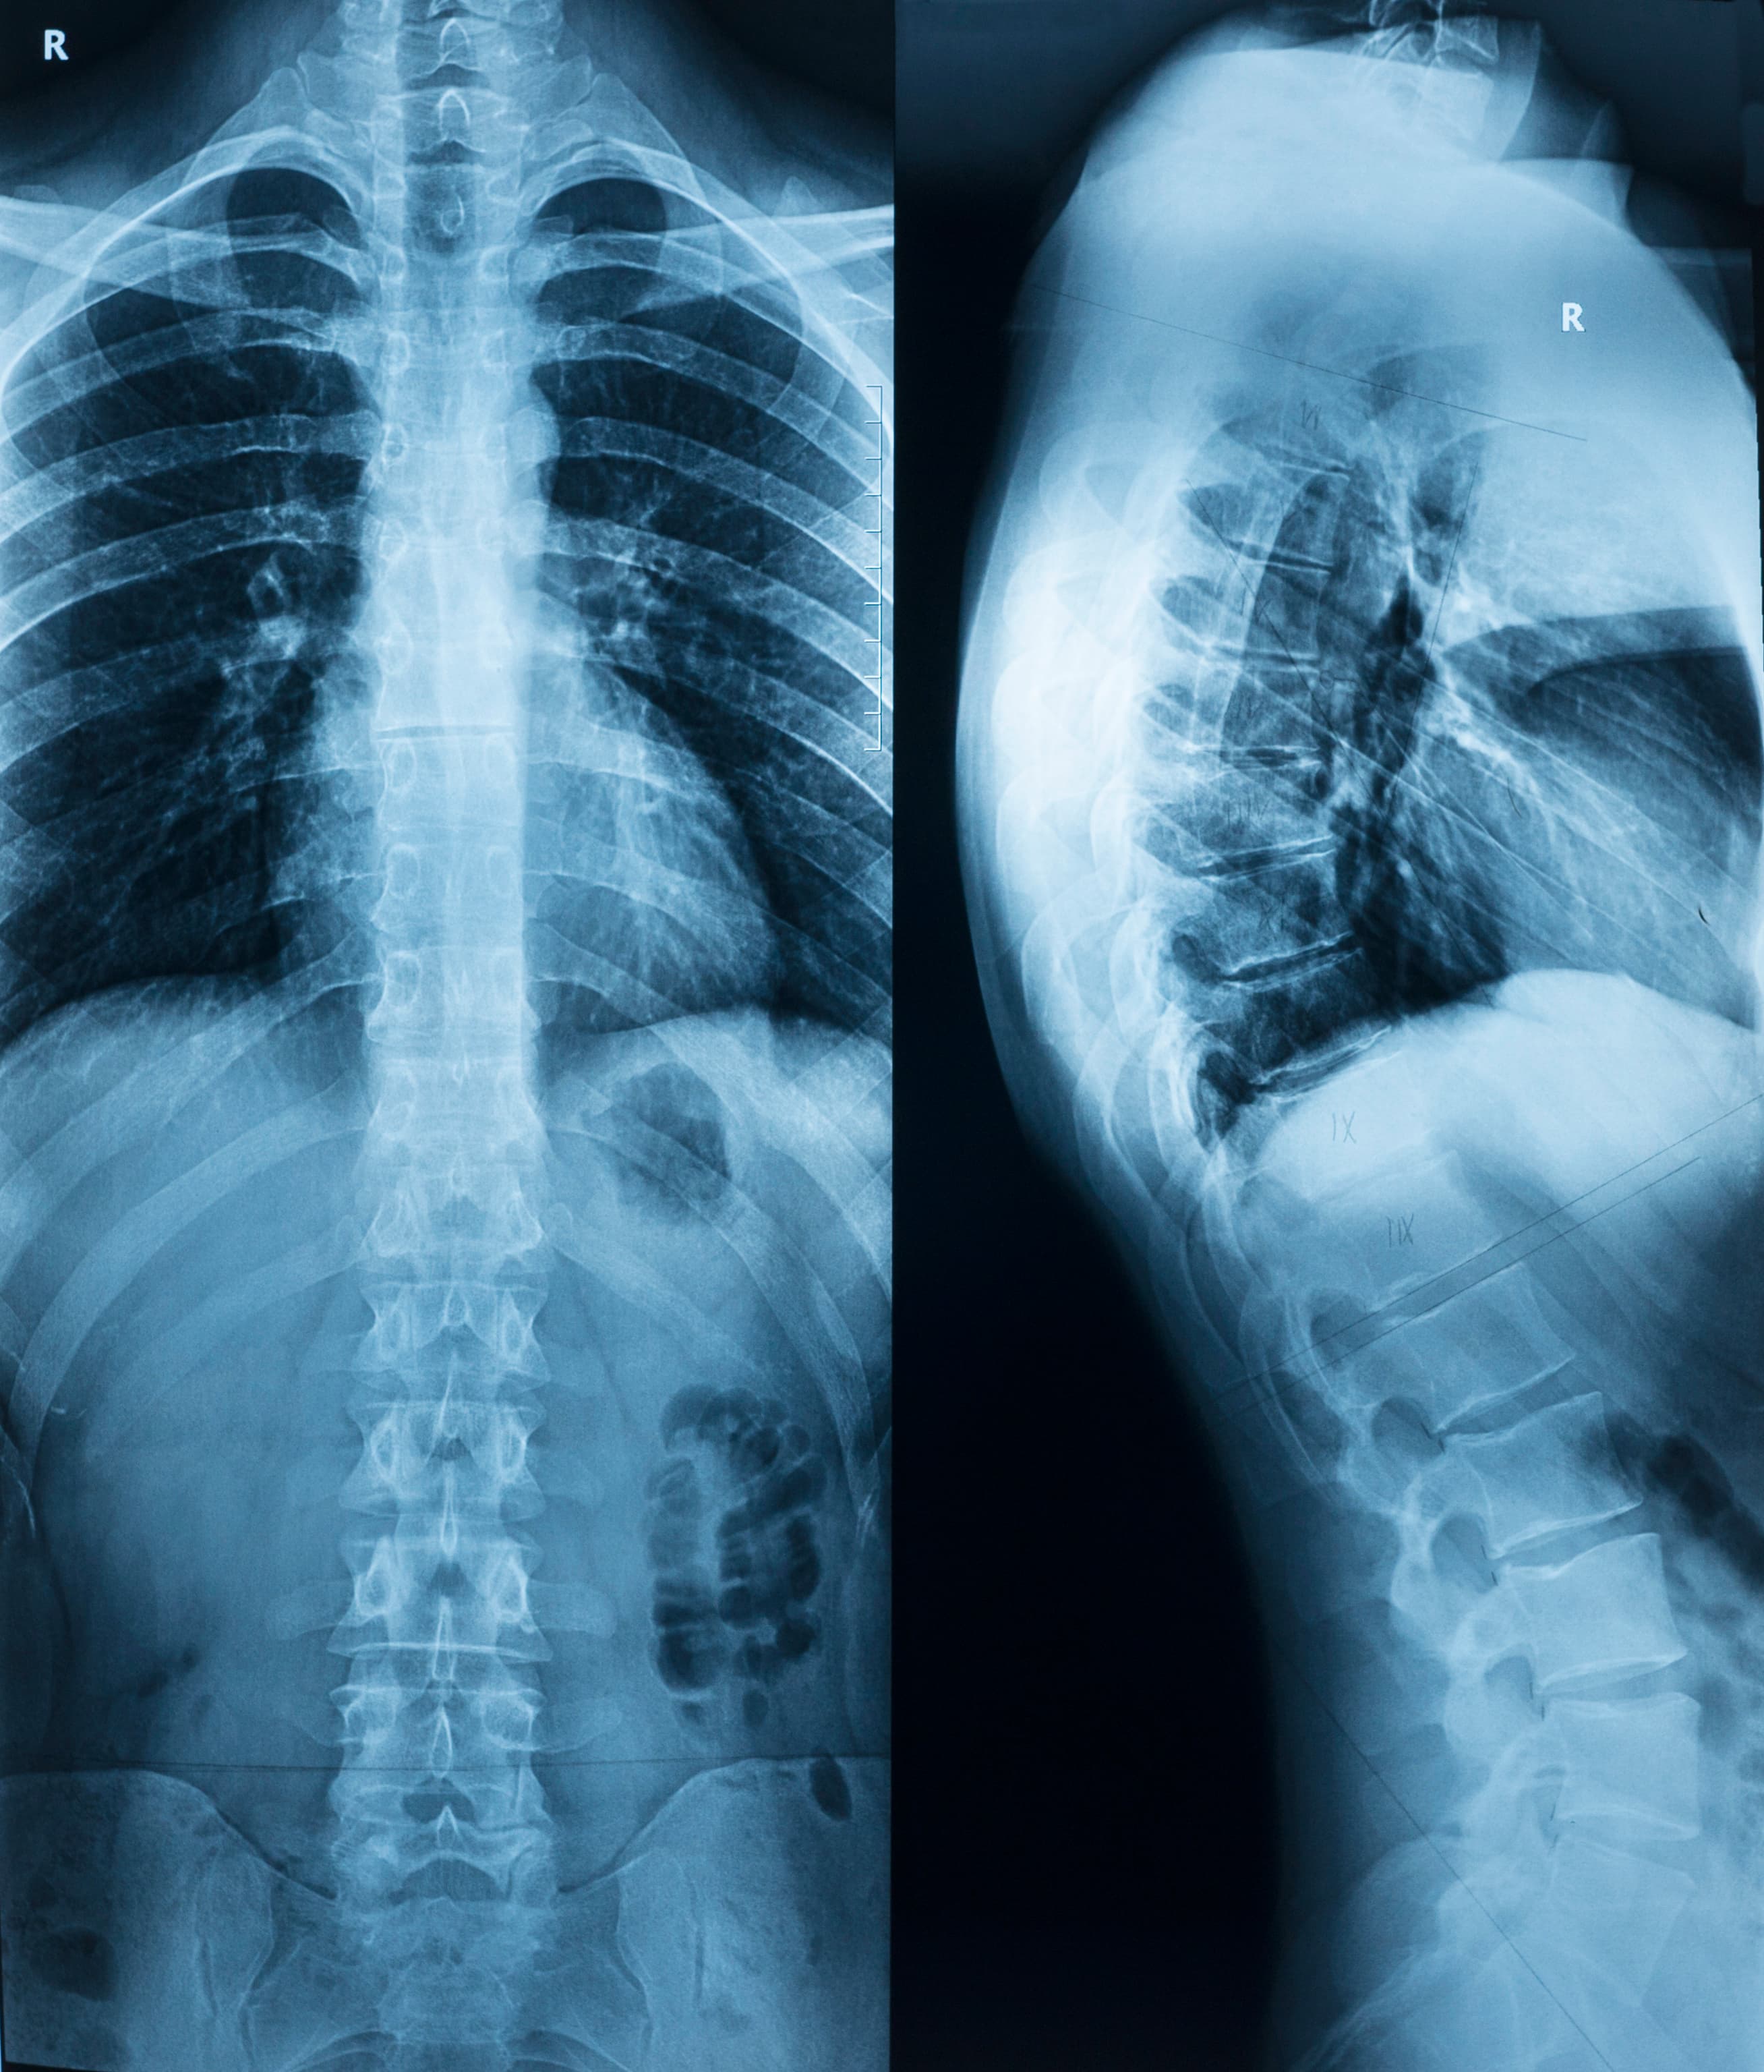

Dr. Damouni is very articulate and passionate about his work. An x ray along with an examination let us know that my sacrum is severely out of place. I now finally know w...More

I absolutely love seeing Labib Damouni at Forefront Chiropractic! I first came in with a back injury a couple years ago, and have felt completely taken care of ever since. He takes his time expressing all concerns, and answers any and all questions with heart. You can tell he truly cares about his patients and work, and helping people gain optimal health. He practices the Gonstead chiropractic method, which is the safest and best form of care for your spine! I cannot recommend him enough!...More